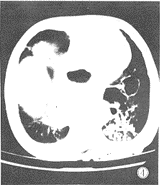

图4 CT扫描显示左心后缘肺大泡征。

2.2 CT平扫

左下肺心后缘可见圆形及卵圆形含气液腔,胃腔内无气 体时呈软组织块影,边缘光滑,周围无卫星灶,无胸膜反应, CT诊断左下肺占位、肺脓肿、肺大泡、肺隔离症、支气管含气 液囊肿及肺包虫囊肿。